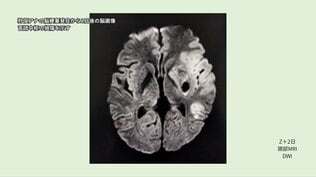

【言葉を失ったアナウンサー】脳梗塞による失語症 リハビリを「楽しんだ」 陰で猛烈な努力… こなした膨大なプリント、学習ドリル【第2話】

【言葉を失ったアナウンサー】脳梗塞による失語症 “回復は常に道の途中” 「僕の人生は、まだ終わっていない」【第3話】